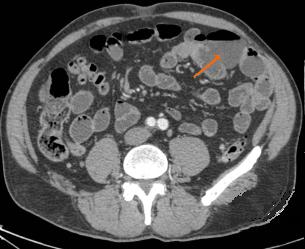

Aspect radiologique TDM de diverticule duodenale

et de l'intestin grele est image d'une contenue a iso-dense

a paroi mince , lisse a hyperdense . A l'intestin image de

air-liquid est frequemment se voyait .

Diverticule de D2 en coupe TDM axiale |